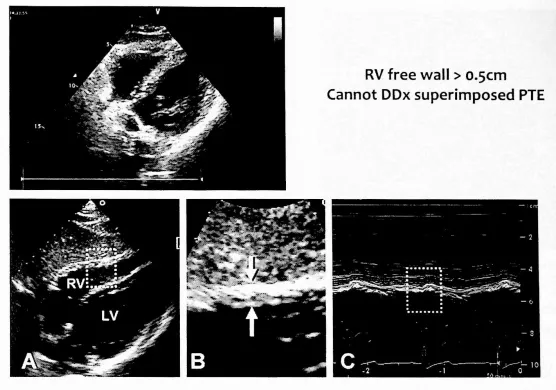

RV free wall thickness : 정상 3 ~ 5 mm

RV hypertrophy = Chronic RV failure 의미

RV free wall 두께 > 5 mm 면 우심실 비대

RV free wall 두께 > 5 mm 이면 PTE R/O 못함

≤ 5 mm suggests acute RV dysfunction

5 mm suggests chronic RV dysfunction

엔듀런스 운동선수는 RV가 확장되면서 RV free wall이 두꺼워질 수 있다.

Supplementary Video 2. (a, b, and c): Right Ventricular Free Wall Thickness